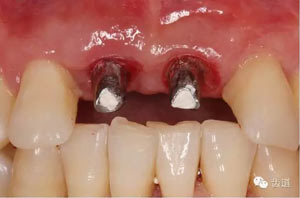

袖口形態(tài)

基臺就位